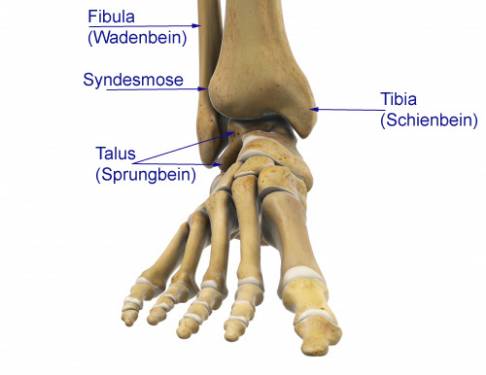

Unter einer Sprunggelenksfraktur versteht man Frakturen der Knöchelregion: Es kommen sowohl isolierte Frakturen des Außenknöchels oder des Innenknöchels vor. Die Mehrzahl aller Frakturen betrifft aber den aus dem Wadenbein (Fibula) bestehenden Außenknöchel. Auch Kombinationsverletzungen beider Knöchel sind möglich. Man spricht dann von einer bimalleolären Fraktur des Sprunggelenks, wenn Fibula (Wadenbein, außen) und Tibia (Schienbein, innen) betroffen sind.

Die Einteilung der Sprunggelenksfrakturen erfolgt systematisch anhand der Lage der Fraktur an Innen- und Außenknöchel.

Klassifikation der Sprunggelenksfraktur nach Weber

- Weber-A: Die Fraktur liegt unterhalb der Syndesmose (Bandverbindung zwischen Schienbein und Wadenbein), die Syndesmose ist also nicht beschädigt. Hier ist meistens die Behandlung durch Ruhigstellung (Eingipsen) ausreichend.

- Weber-B: Bei der Weber-B-Verletzung ist der Bereich um die Syndesmose in die Fraktur miteinbezogen. Die Syndesmose kann auch gerissen sein. Meistens ist bei der Weber-B-Verletzung des Sprunggelenks eine operative Behandlung der Fraktur notwendig.

- Weber-C: Hier liegt die Fraktur oberhalb der Syndesmose. Deswegen ist die Syndesmose immer auch gerissen. Die Membran zwischen Schienbein und Wadenbein (Membrana interossea cruris) ist meistens auch verletzt. Diese Weber-C-Verletzung des Sprunggelenks wird in einer bestimmten Ausprägung auch als Maisonneuve-Fraktur bezeichnet. Auch bei der Weber-C-Fraktur ist eine operative Versorgung notwendig, um die Sprunggelenksgabel wiederherzustellen.

Die Rolle der Syndesmose

In schweren Fällen erfolgt die Fraktur des Sprunggelenks mit Beteiligung der Syndesmose. Die Syndesmose ist die flächige Bandverbindung zwischen Schienbein und Wadenbein. Sie stabilisiert die Sprunggelenksgabel und hält sie zusammen. Bei Beschädigung der Syndesmose bei Sprunggelenksfrakturen besteht die Gefahr, dass die Sprunggelenksgabel dauerhaft instabil bleibt. Die Destabilisierung der Sprunggelenksgabel ist eine wichtige Ursache für die Arthrose des Sprunggelenks, wenn sie nicht rechtzeitig versorgt wird. Daher ist die Beteiligung der Syndesmose das Kriterium, nach der die Einteilung von Sprunggelenksfrakturen erfolgt.